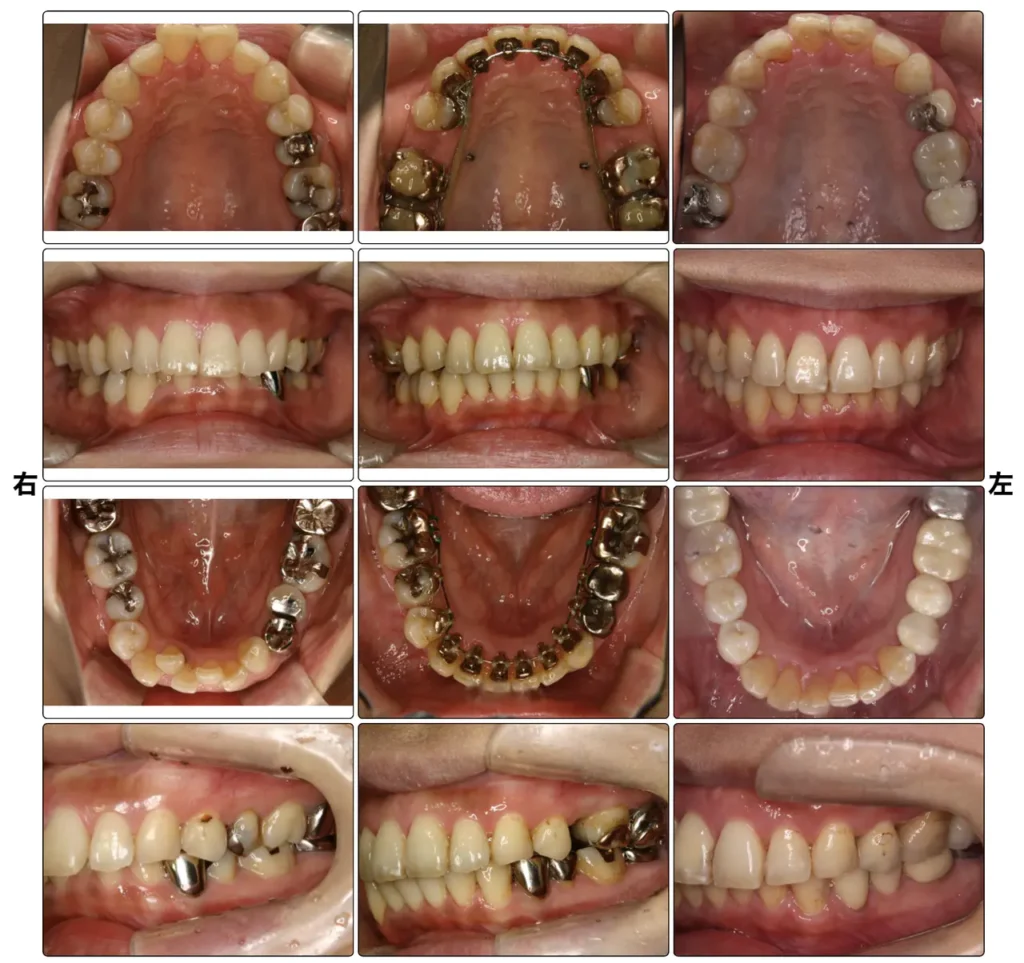

症例2 上顎前突、叢生

「出っ歯がきになる。」

舌側矯正治療(装置名:インコグニート)150万円 月1回の調整(7,000円)

舌側矯正(歯の内側矯正)で対応、上顎のみ小臼歯抜歯。銀歯も被せ直しました。

治療期間2.5年。右が、術後5年後。

上顎前突症(出っ歯)は、歯並びの次に相談の多い不正咬合です。大人の出っ歯の矯正治療の場合は、程度によりますが、抜歯を伴う治療になることもがあります。この症例も舌側矯正(歯の裏側)を行いました。

症例3 叢生

「歯並びがきになる。」

アライナー治療(インビザライン )片顎500,000円 ワイヤー矯正(セラミックブラケット)550,000円 月1回の調整(7,000円)

左より、術前、術中(小休止抜歯)、治療終了3年後。上下顎小臼歯抜歯、上顎マウスピース矯正、下顎セラミックブラケットワイヤー矯正(治療期間1年半)

軽い叢生の場合は、マウスピースタイプの矯正治療で十分可能です。今回のようなよく見える上顎の方をマウスピース矯正や舌側矯正、下顎を普通のワイヤー矯正で、と組み合わすことも可能です。